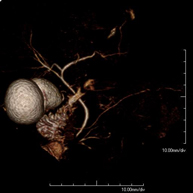

- Angio-RM Aorta iliaca

Prueba diagnóstica no invasiva que consiste en el estudio de la arteria aorta abdominal, obteniendo imágenes de alta definición anatómica mediante el empleo de un campo electromagnético y ondas de radio (con un emisor y un receptor). Es indispensable el uso de contraste intravenoso paramagnético (gadolinio). Sin embargo, no utiliza radiación ionizante. La calidad de las imágenes permite realizar reconstrucciones en 2D y 3D. Esta prueba está especialmente indicada como estudio pre-quirúrgico (mapa vascular) antes de intervenciones percutáneas o quirúrgicas de aorta abdominal, estudio complementario en pacientes con isquemia de miembros inferiores…